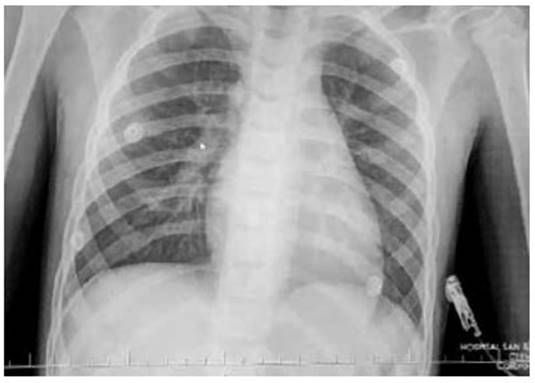

Ingresa a consultorio externo por presentar tiempo de enfermedad de 15 días con dolor de garganta, tos esporádica y cansancio, fiebre que cedía con Paracetamol; 2 días antes presenta diaforesis, malestar general y 1 día antes se agregan náuseas y vómitos más frialdad distal y dolor torácico. Es evaluado con FC: 145 x’, PA: 73/52 mmHg. taquipneico, pálido y con frialdad distal, los ruidos cardiacos con leve disminución del tono, no soplos, no visceromegalias; es referido a trauma shock de emergencia donde se le brinda fluidos en bolo Endovenoso, con dobutamina y noradrenalina. Y manejo antibiótico con ceftriaxona y macrólido Los exámenes auxiliares (Tabla 01) muestra: Hemograma leu 18410 /µL, Hemoglobina (Hb) 14.9gr/ dL, plaquetas: 322700 /µL, lactato 3.1 Ph 7.4 deshidrogenasa láctica(DHL): 1884 IU/L , alanina aminotransferasa (TGP): 1212 IU/L aspartato aminotransferasa (TGO): 1754 IU/L , creatina- fosfocinasa (CPK)total 3471 ng/ml, Troponina I: 7164 Pg/ml. IFI viral negativo, Core Total Hep B, hepatitis A IgM, hepatitis C (no reactivos) IgM para Mycoplasma Pneumonae (positivo) y Mycoplasma pneumonae (Reactivo). La Radiografía de tórax (Figura N°1) muestra leve cardiomegalia y refuerzo parahiliar derecho, el EKG (Figura N°2) se observó complejos QRS de bajo voltaje, taquicardia sinusal y leve supradesnivel del segmento ST. El ecocardiograma (Figura 3 A y B) efusión pericárdica moderada, dilatación de Vena cava inferior, pericardio engrosado, FEVI (fracción de eyección del ventrículo izquierdo) 66%, Ventrículo derecho disminuido. Con todo esto y los datos de laboratorio se establece el diagnostico de Miopericarditis.

Figura N°1 Radiografía de tórax: imagen muestra leve cardiomegalia y refuerzo parahiliar derecho.